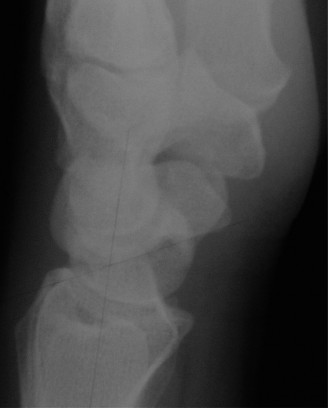

CASE 11 ### A patient presents to your clinic with ulnar-sided wrist pain. X-ray is as shown in Figure 3–10. What is your diagnosis?

Figure 3–10(©) Sunil Thirkannad and Christine M. Kleinert.

The correct answer is (D). The findings in the radiographs are consistent with pisotriquetral arthritis.